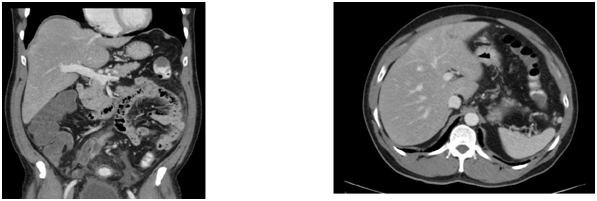

In view of the elevated Troponin I, the patient was initially treated as for Non-ST elevated myocardial infarction (NSTEMI). He was immediately started upon dual anti-platelet therapy together with low molecular weight heparin and subsequently underwent an emergent coronary angiogram which showed minor coronary artery disease. Computed Tomography of Pulmonary Arteries was also performed which showed no evidence of pulmonary embolism (Figure 2). The anti-platelet and low molecular weight heparin was then stopped. However, his gastro-intestinal symptoms worsened and he started to spike a temperature once more in the ward. He complained of persistent abdominal pain despite bowel clearance with laxatives. Computed Tomography of Abdomen and Pelvis was performed. The result showed long segment rectal wall thickening seen with peri-rectal fat stranding which was initially thought to be related to aggressive laxative consumption , but malignancy and infection should be ruled out with suggestion of endoscopy; extensive omental fat stranding, most prominent in the upper abdomen abutting the anterior wall of the transverse colon where there was thickening of the anterior transverse colonic wall to rule out possibility of underlying malignancy; peritoneal fat stranding and nodularity seen with minimal ascites; small volume but rounded inferior mensenteric and para-aortic lymph nodes seen.

Figure 3 CT abdomen and Pelvis.

1. NON- specific long segment thickening of the rectal wall; soft tissue and extensive fat stranding are seen in t he mesorectum. Omental fat stranding is most promi nent in the upper abdomen abutting the anterior wall of transverse colon; thickening of the anterior transverse colon wall abutting the omental stranding.

2. 0.6cm splenenculi are seen in close relation to the anterior pole of the spleen.

3. A 1.6x1.2cm enlarged celiac node is noted.

4. Small volume, but round lymph nodes are seen along the inferior mesenteric artery and the para -aortic region, the largest in the para- aortic region measures 0.9x0.8cm.